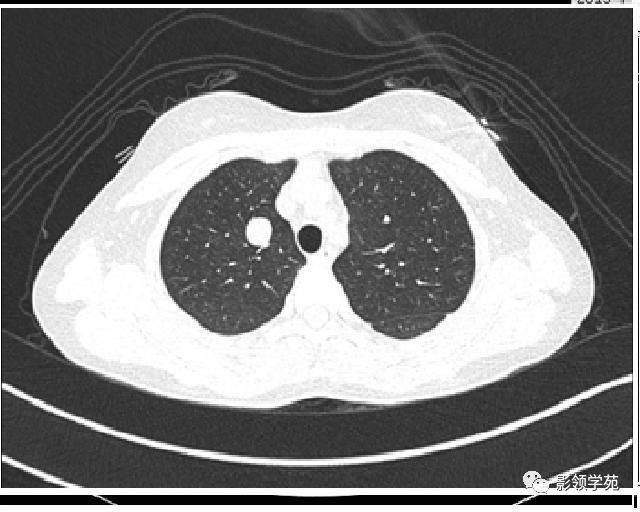

肺部有阴影CT

肺部阴影图片

肺部阴影图片胸片

正常肺部ct图

正常肺部ct片